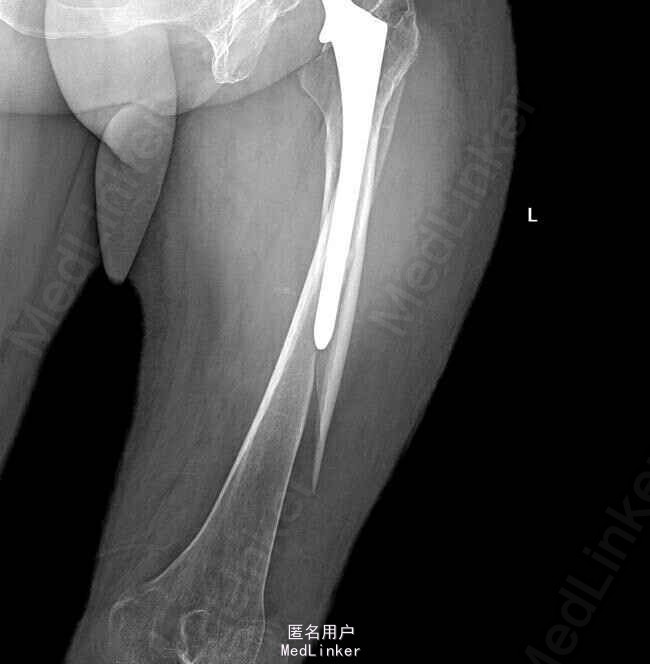

老年女性,10年行“左侧人工髋关节置换术”,1周前从三轮车摔下,左侧肢体着地,出现下肢明显疼痛伴活动,后左下肢出现肿胀

左髋部可见长度约15cm的陈旧手术切口,左下肢外旋约45度,肿胀明显,大腿中下1/3外侧压痛明显 左股骨X线片:左侧股骨干骨折;左侧全髋置换术后。